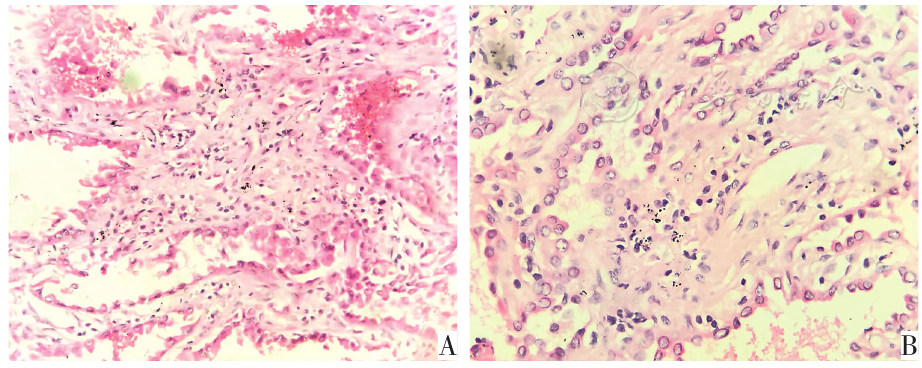

图2 两组肺结节患者组织病理学结果。图A为穿刺活检术后病理结果显示为腺癌(HE 10×40);图B为穿刺活检术后病理结果为腺癌(HE 10×40)